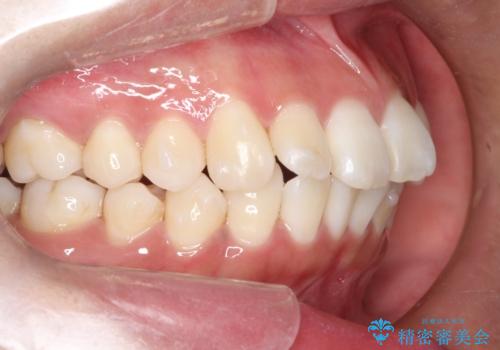

がたがたをインビザラインで整った歯並びへ

- 全体的ながたつきを主訴に来院されました。

抜歯矯正も考えられる状態でしたが、患者様が非抜歯での矯正を希望されたため、歯と歯の間をわずかに削りスペースを作り、全体を整える計画としました。

非常に協力的な患者様でしたので、スムーズに治療を終えることができました。